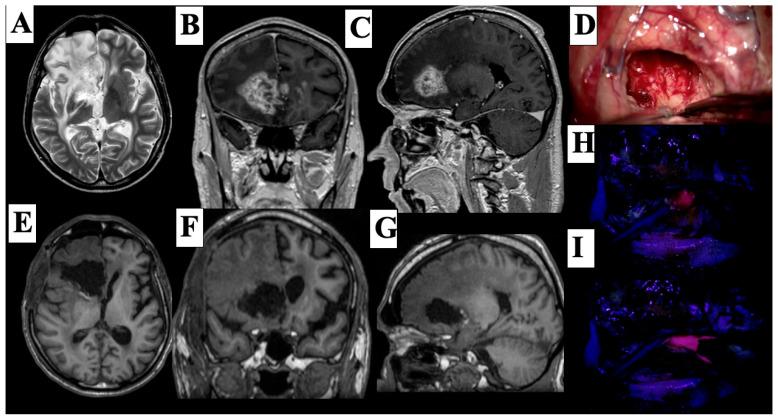

Background High-grade gliomas (HGGs) are aggressive brain tumors with poor prognoses. Maximizing the extent of resection (EOR) is a critical surgical goal. Fluorescence-guided surgery using 5-aminolevulinic acid (5-ALA) has been proposed to enhance tumor visualization and resection. MethodsWe retrospectively analyzed 141 patients with histologically confirmed HGGs who underwent either 5-ALA-guided ( = 71) or conventional white-light ( = 70) resection between 2018 and 2023. Propensity score matching and multivariate Cox regression models were used to assess the impact of 5-ALA on surgical outcomes and survival. Results: Gross total resection (GTR) was significantly more common in the 5-ALA group than the conventional white-light group (28.17% vs. 12.86%, = 0.0245). Kaplan-Meier analysis showed no statistically significant difference in overall survival between groups after matching (log-rank = 0.6371). However, patients with GTR had significantly improved survival compared to those with subtotal resection (log-rank = 0.0423). Multivariate Cox regression identified radiotherapy (HR = 0.291, 95% CI: 0.166-0.513, < 0.001), higher Karnofsky Performance Status (HR = 0.962, 95% CI: 0.942-0.982, = 0.0003), and GTR (HR = 0.476, 95% CI: 0.272-0.834, = 0.0091) as independent predictors of improved survival. 5-ALA usage was not an independent predictor (HR = 0.885, 95% CI: 0.554-1.413, = 0.612). Radiotherapy and chemotherapy were more frequently administered in the conventional white-light group ( = 0.0404 and = 0.0085, respectively). Conclusions 5-ALA fluorescence-guided surgery significantly increases the rate of gross total resection in high-grade glioma patients but does not independently confer a survival advantage. Survival outcomes are primarily influenced by the extent of resection, adjuvant therapy, and functional status. Integration of 5-ALA within a comprehensive oncological framework may enhance its clinical utility.

背景

高级别胶质瘤(HGGs)是预后较差的侵袭性脑肿瘤。最大化切除范围(EOR)是关键的手术目标。已提出使用5-氨基乙酰丙酸(5-ALA)进行荧光引导手术以增强肿瘤可视化和切除效果。

方法

我们回顾性分析了2018年至2023年间141例经组织学确诊为HGGs且接受了5-ALA引导切除(n = 71)或传统白光切除(n = 70)的患者。采用倾向评分匹配和多变量Cox回归模型来评估5-ALA对手术结果和生存的影响。

结果

5-ALA组的全切除(GTR)明显比传统白光组更常见(28.17%对12.86%,P = 0.0245)。Kaplan-Meier分析显示匹配后两组间总生存无统计学显著差异(对数秩检验P = 0.6371)。然而,与次全切除患者相比,GTR患者的生存有显著改善(对数秩检验P = 0.0423)。多变量Cox回归确定放疗(HR = 0.291,95%CI:0.166 - 0.513,P < 0.001)、较高的卡诺夫斯基功能状态(HR = 0.962,95%CI:0.942 - 0.982,P = 0.0003)和GTR(HR = 0.476,95%CI:0.272 - 0.834,P = 0.0091)是生存改善的独立预测因素。5-ALA的使用不是独立预测因素(HR = 0.885,95%CI:0.554 - 1.413,P = 0.612)。传统白光组放疗和化疗的应用更频繁(分别为P = 0.0404和P = 0.0085)。

结论

5-ALA荧光引导手术显著提高了高级别胶质瘤患者的全切除率,但并未独立带来生存优势。生存结果主要受切除范围、辅助治疗和功能状态的影响。将5-ALA整合到综合肿瘤学框架内可能会提高其临床效用。